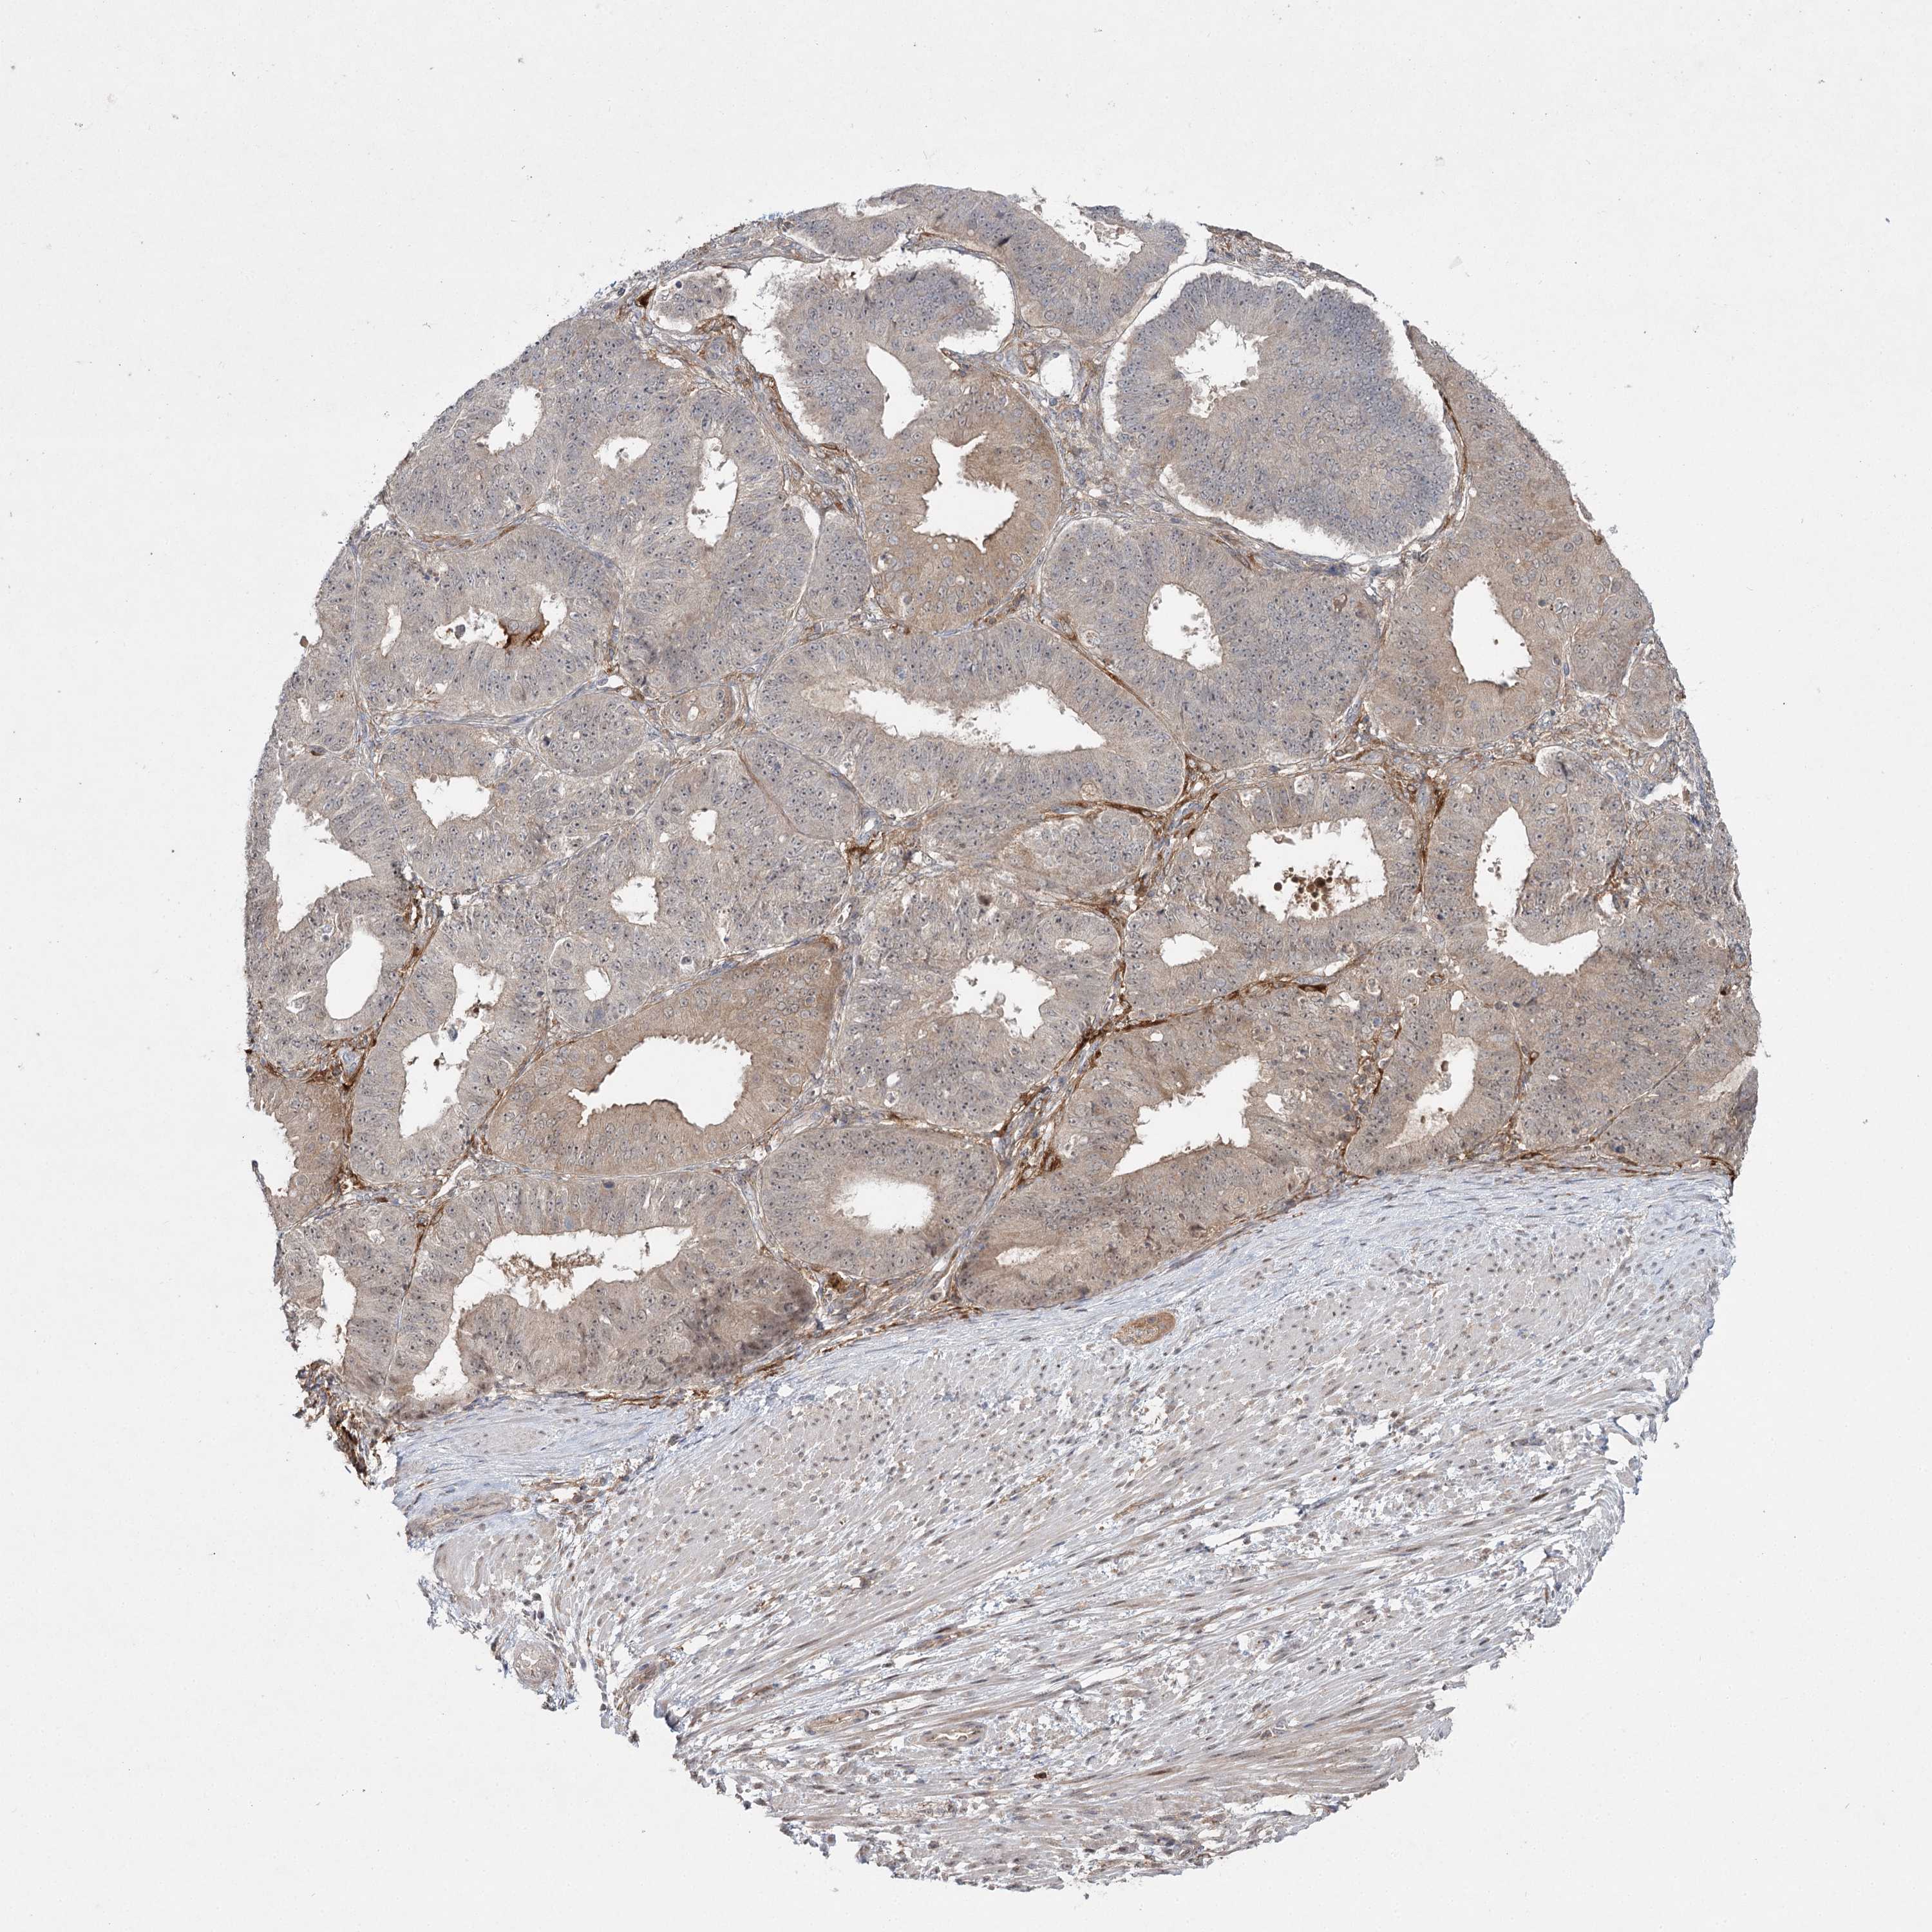

OVARIAN CANCER - Protein expressioni

A mouse-over function shows sample information and annotation data. Click on an image to view it in a full screen mode. Samples can be filtered based on level of antibody staining by selecting one or several of the following categories: high, medium, low and not detected. The assay and annotation is described here.

Note that samples used for immunohistochemistry by the Human Protein Atlas do not correspond to samples in the TCGA dataset.

Antibody stainingi

Antibody staining in the annotated cell types in the current human tissue is reported as not detected, low, medium, or high, based on conventional immunohistochemistry profiling in selected tissues. This score is based on the combination of the staining intensity and fraction of stained cells.

Each image is clickable and will lead to virtual microscopy that enables deeper exploration of all samples and also displays staining intensity scores, fraction scores and subcellular localization as well as patient and tissue information for each sample.

Antibody HPA038084

Cystadenocarcinoma, serous, NOS

Carcinoma, endometroid

Cystadenocarcinoma, mucinous, NOS

Carcinoma, NOS